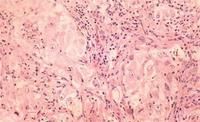

病理

神經膠質瘤在顱內各種腫瘤中最為多見。在神經膠質瘤中以星形細胞瘤為最常見,其次為多形性膠質母細胞瘤,室管膜瘤占第三位。根據北京市宣武醫院和天津醫學院附屬醫院的統計,在2573例神經膠質瘤中,分別占39.1%、25.8%和18.2%。